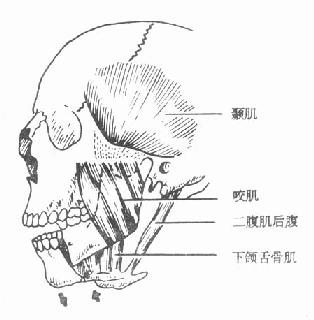

下颌骨骨折段的移位,主要是因肌肉牵拉所致。颏孔部骨折时,前骨折段常因降颌肌群的牵拉而向下移位,后骨折段常因升颌肌群的牵拉而向上移位(图4-14)。颏部的粉碎性骨折,中部骨折段由于颏舌肌、颏舌骨肌牵拉而向后移位。两侧骨折段由于下颌舌骨肌、舌骨舌肌的牵拉向中线移位,使下颌骨前部弓形变窄。这种骨折可引起舌后坠而发生呼吸困难,甚至发生窒息,应特别注意。髁状突骨折,多因间接受力所致,可与颏部骨折同时发生,应注意检查以免漏诊。髁状突骨折后,常因翼外肌的牵拉,向前内方移位,同时下颌升支因升颌肌群牵拉而向上移位,出现前牙不能闭合的状态。如双侧髁状突骨折,则前牙开牙合更明显(图4-15)。

| 图4-14 颏孔部骨折后骨折段移位情况 | 图4-15 髁状突骨折后骨折段的移位 |